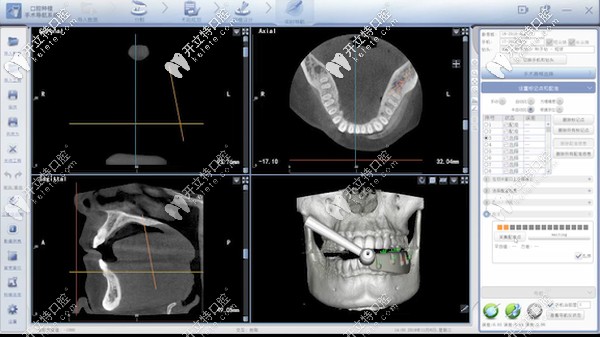

據(jù)了解:口腔種植數(shù)字化動態(tài)導(dǎo)航是種植牙當(dāng)中的黑科技,主要通過計算機(jī)重建患者口腔頜骨三維立體模型。

數(shù)字化動態(tài)導(dǎo)航種植技術(shù)

它就像汽車導(dǎo)航一樣,通過顯示屏實(shí)時直觀地看到種植體植入頜骨的全過程,全程監(jiān)控種植位點(diǎn)、角度、深度。

能夠避免損傷重要的解剖結(jié)構(gòu),給患者提供更加安全、精準(zhǔn)、高效的體驗(yàn)。